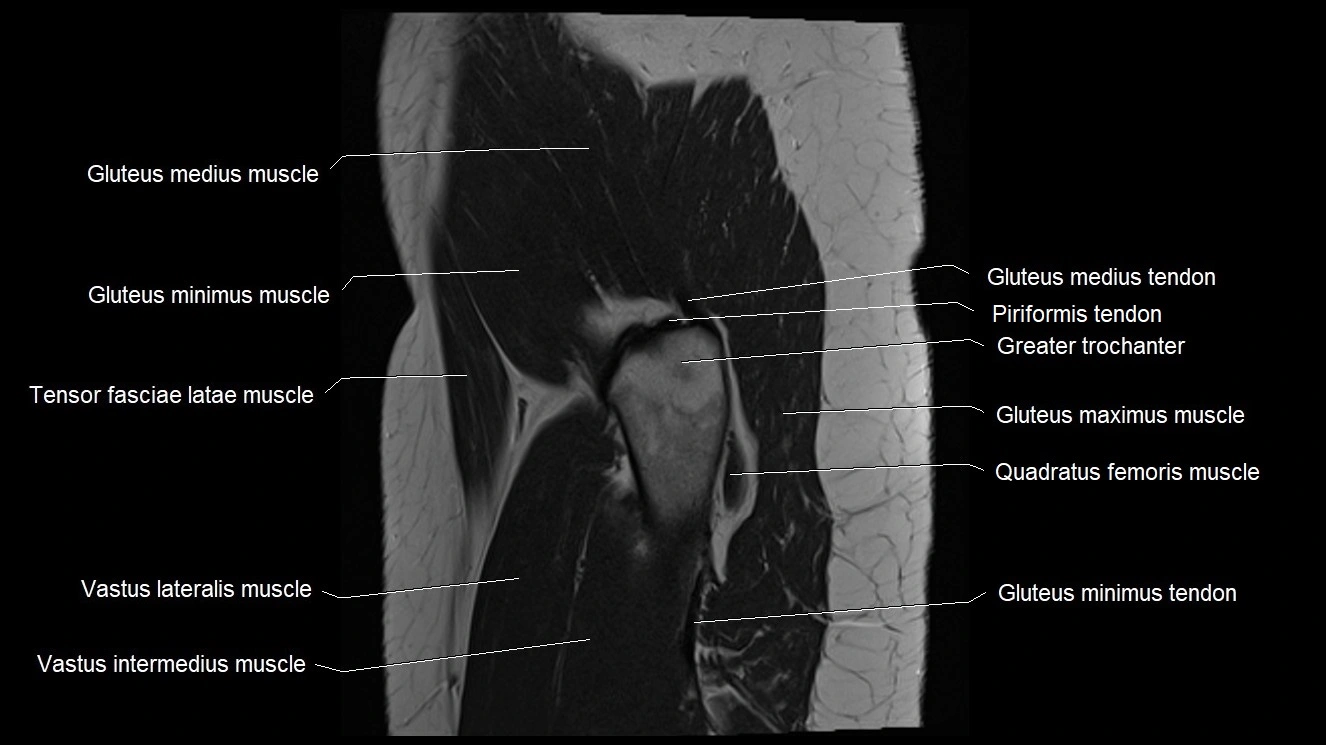

- Gluteus medius muscle

- Gluteus medius tendon

- Gluteus minimus muscle

- Gluteus minimus tendon

- Greater trochanter

- Gluteus maximus muscle

- Quadratus femoris muscle

- Tensor fasciae latae muscle

- Vastus intermedius muscle

- Vastus lateralis muscle